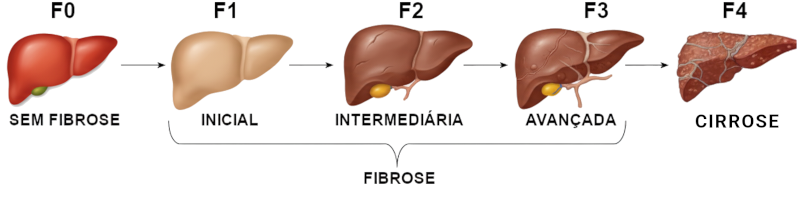

Na grande maioria dos casos, o hepatocarcinoma surge em fígados com cirrose. Ele pode também surgir em fígados normais de pessoas expostas a aflatoxina (encontrada em amendoins contaminados, por exemplo) ou em fígados já doentes, mas ainda sem cirrose, em pacientes portadores de esteato hepatite não alcoólica, hepatite B crônica e hemocromatose, mas esses são exceção – quase todos surgem em portadores de cirrose hepática.

A cirrose hepática é o processo final de diversas doenças do fígado: as hepatites, as lesões pelo álcool, o uso de certas medicações, a hemocromatose (acúmulo de ferro) e as colangites, entre outras. Todas essas doenças provocam a destruição dos hepatócitos, lentamente, com a formação de cicatrizes no interior do fígado, determinando a cirrose. Ao contrário do que se pensa, a maioria das cirroses atualmente são causadas pelas hepatites B e C e pela esteato-hepatite não alcoólica. O alcoolismo ainda é um fator importante, mas não necessariamente naquelas pessoas que ingerem altas doses de álcool. Mesmo doses mais modestas (três a quatro garrafas de cerveja por semana) podem levar à cirrose.

O hepatocarcinoma surge do mesmo processo de destruição e multiplicação de células que leva à cirrose, através de mecanismos ainda não bem esclarecidos. De um modo geral, considera-se que uma pessoa portadora de cirrose silenciosa ou pouco sintomática tenha um risco de 5% ao ano de desenvolver um hepatocarcinoma.